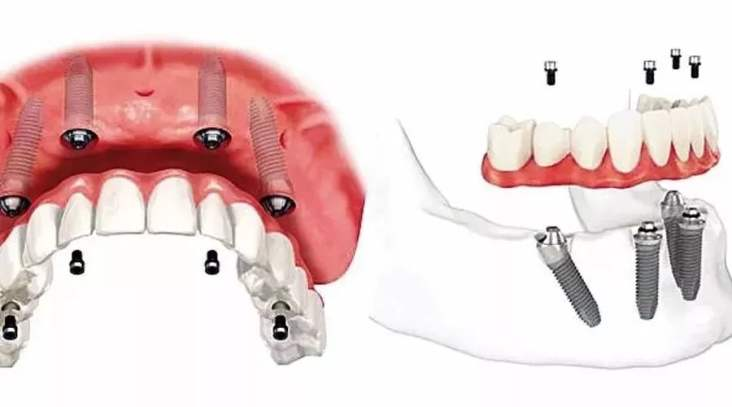

3、种植修复

适用于:各种多颗牙、半口牙甚至全口牙齿的缺失。

优 点:恢复咀嚼功能*多的修复方式,属于固定修复,不能自行取下。

缺 点:费用较高,修复周期较长,有些还需要植骨。修复周期从拔牙算起得半年以上的时间。